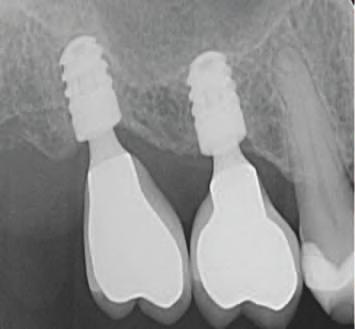

În zonele edentate cu d sponb l tate osoasă comprom să în d mens un le vert cale sau or zontale, mplantur le scurte ș /sau cu d ametru îngust sunt modal tăț alternat ve de tratament la procedur le de grefare osoasă pentru plasarea convenț onală (f g. 1, 2). Implantur le scurte (lung mea <10 mm) pot f plasate fără grefare osoasă vert cală. În general, lățmea mplantulu este cons derată ma mportantă decât lung mea acestu a pentru d s parea stresulu . Zona osulu crestal pr mește pres unea max mă, ar spre porț unea ap cală a mplantulu se

Figurile:

1. Utilizarea implanturilor scurte (lungime 6 mm) pentru a evita o augmentare cu grefă de sinus.

2. Utilizarea mai multor implanturi de dimensiuni mici, de tip monobloc, pentru a restaura o arcadă maxilară edentată îngustă fără grefare.